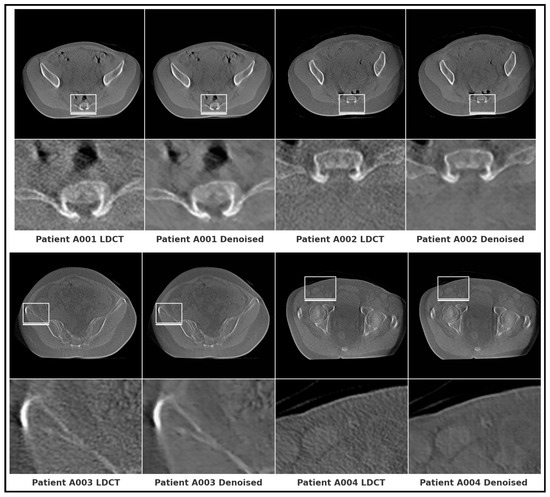

High-Fidelity CT Image Denoising with De-TransGAN: A Transformer-Augmented GAN Framework with Attention Mechanisms

by Usama Jameel and Nicola Belcari

Low-dose computed tomography (LDCT) has become a widely adopted protocol to reduce radiation exposure during clinical imaging. However, dose reduction inevitably amplifies noise and artifacts, compromising image quality and diagnostic confidence. To address this challenge, this study introduces De-TransGAN, a transformer-augmented Generative Adversarial [...] Read more.

Low-dose computed tomography (LDCT) has become a widely adopted protocol to reduce radiation exposure during clinical imaging. However, dose reduction inevitably amplifies noise and artifacts, compromising image quality and diagnostic confidence. To address this challenge, this study introduces De-TransGAN, a transformer-augmented Generative Adversarial Network specifically designed for high-fidelity LDCT image denoising. Unlike conventional CNN-based denoising models, De-TransGAN combines convolutional layers with transformer blocks to jointly capture local texture details and long-range anatomical dependencies. To further guide the network toward diagnostically critical structures, we embed channel–spatial attention modules based on the Convolutional Block Attention Module (CBAM). On the discriminator side, a hybrid design integrating PatchGAN and vision transformer (ViT) components enhances both fine-grained texture discrimination and global structural consistency. Training stability is achieved using the Wasserstein GAN with Gradient Penalty (WGAN-GP), while a composite objective function—L1 loss, SSIM loss, and VGG perceptual loss—ensures pixel-level fidelity, structural similarity, and perceptual realism. De-TransGAN was trained on the TCIA LDCT and Projection Data dataset and validated on two additional benchmarks: the AAPM Mayo Clinic Low Dose CT Grand Challenge dataset and a private clinical chest LDCT dataset comprising 524 scans (used for qualitative assessment only, as no NDCT ground truth is available). Across these datasets, the proposed method consistently outperformed state-of-the-art CNN- and transformer-based denoising models. On the LDCT and Projection dataset head images, it achieved a PSNR of 44.9217 dB, SSIM of 0.9801, and RMSE of 1.001, while qualitative evaluation on the private dataset confirmed strong generalization with clear noise suppression and preservation of fine anatomical details. These findings establish De-TransGAN as a clinically viable approach for LDCT denoising, enabling radiation reduction without compromising diagnostic quality. Full article